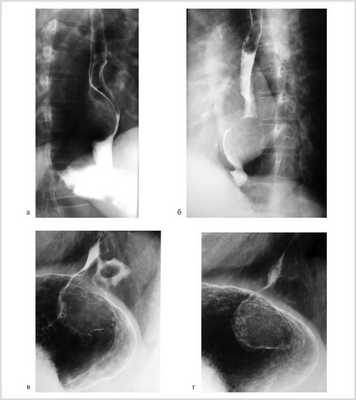

Рентгенологически у 8 (61,5%) больных опухоль локализовалась в нижнегрудном отделе пищевода, у 1 (7,7%) дефект наполнения с четкими контурами располагался на уровне V грудного позвонка (рис. 1, а, б).

Рис. 1. Рентгенограммы пищевода больных с лейомиомой пищевода (а, б) и пациента с лейомиомой пищевода, сочетанной с кардиальной грыжей пищеводного отверстия диафрагмы (в, г).

У 3 (23,1%) пациентов кардиальный отдел желудка, у 1 (7,7%) больного — кардия и дно желудка были смещены в заднее средостение. Дефект наполнения пищевода у этих пациентов был расположен непосредственно выше области пищеводно-желудочного перехода (см. рис. 1, в, г).